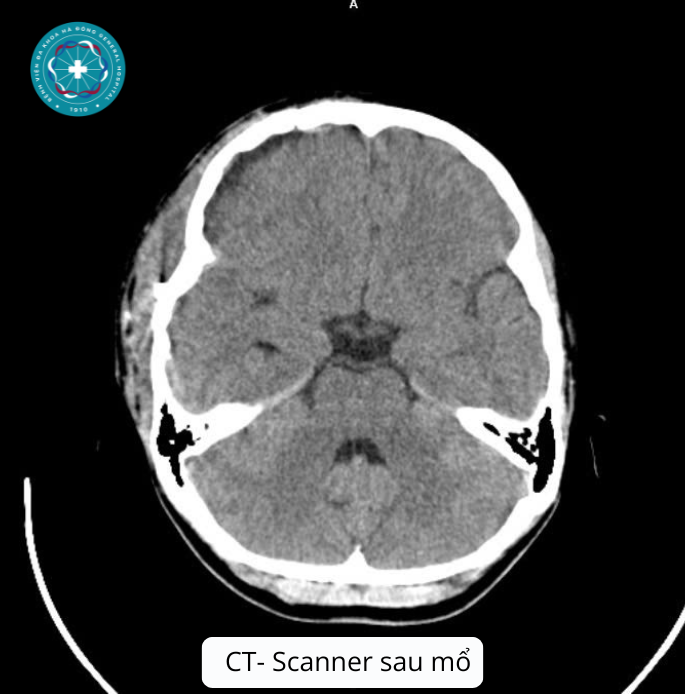

- Qua thăm khám lâm sàng và hình ảnh chụp CT-Scanner sọ não, các bác sĩ phát hiện khối Máu tụ ngoài màng cứng vùng thái dương đỉnh trái với kích thước rất lớn (78x16x82 mm), kèm tụ khí nội sọ, vỡ xương thái dương trái.

Quá trình phẫu thuật: Các bác sỹ đã thực hiện mở sọ, lấy khối máu tụ ngoài màng cứng và cầm máu thuận lợi. Sự phối hợp nhịp nhàng giữa kíp mổ và kíp gây mê đã giúp ca phẫu thuật diễn ra an toàn, kiểm soát tốt các chỉ số sinh tồn của bệnh nhi.

Kết quả phục hồi: Sau quá trình điều trị hậu phẫu tích cực, bệnh nhân T. đã xuất viện trong tình trạng tỉnh hoàn toàn (Glasgow 15 điểm), vết mổ liền tốt, không để lại bất kỳ di chứng yếu liệt hay tổn thương thần kinh nào.